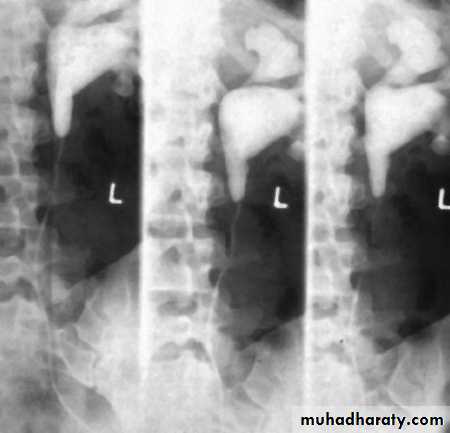

Horse shoe kidney -Kidneys may fail to separate.

-Almost invariably the lower poles remain fused.

-The kidneys axes are more parallel to the spine and malrotated.

-Diagnosis can be made by plain x-ray in some cases.

IVU shows

1. The kidneys at low position .

2.Close to the spine with long axis parallel to the spine .

3. Malrotation manifested by medially directed calyces.

4- The renal pelvis and ureters are anterior and lateral in position .